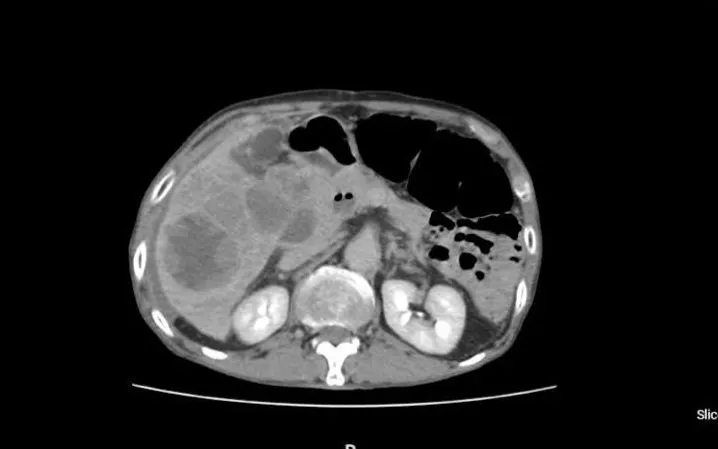

Bệnh nhân nam 77 tuổi, có tiền sử bệnh gan mạn, nhập viện trong tình trạng đau dữ dội vùng hạ sườn phải, mệt lả, tụt huyết áp. Kết quả chụp CT cho thấy nhiều khối u trong gan, trong đó một khối lớn đã bị vỡ, gây chảy máu trong ổ bụng, kèm rối loạn chức năng gan và thiếu máu cấp.